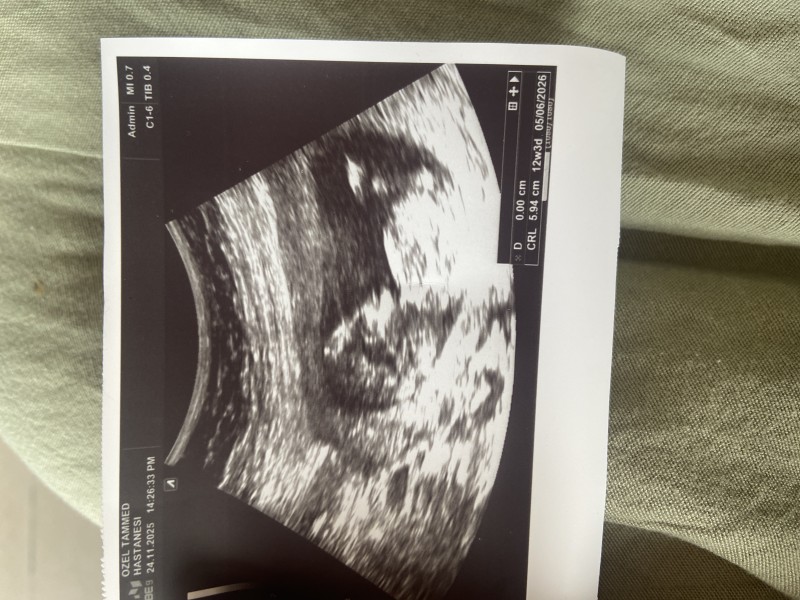

Kızlar 12 haftalık gebeyim cinsiyeti çok merak ediyorum kese şeklinden vs anlayan varsa tahminde bulunur musunuz

Kafa yapısı erkek gibi ama çok anlamam. Bu haftada belli olur artık aslında

Kese yuvarlak değil gibi sanki erkek

Kafa yapısı erkek gıbı valla canm